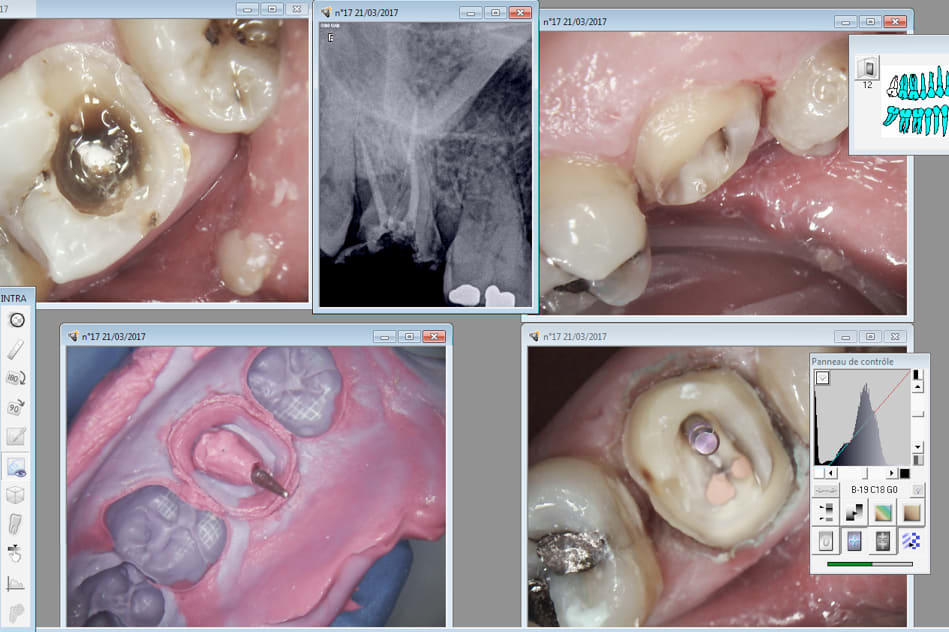

Par contre faut se méfier avec les largo 1. J'ai foré jusqu'à 3 mm de l'apex ( pas moyen de mettre un stop trop fin) , obligé de ré-obturer pour rattraper le coup. -)

Tiencasa c'est à l'aise une endo. Tu ouvres la chambre, tu y colles de l'hypochrorite ensuite tu picores au sx au pif pour trouver les canaux et tu alternes SX-R25. Ensuite tu ouvres légèrement au largo 3. Ca prends 2 minutes et la moitié du boulot est fait. -)

Ensuite tu fais la meme chose avec le R25 et le S1 et 2 minutes après tu es à l'apex en 25 conicité 6. Je parle pour les 3 canaux bien sur. Ici pas trouvé de MV2 mais c'est rare.

Si ca te permet de laisser tomber tes limes K ca sera déjà pas mal. Bon ensuite tu deviens moins conservateur......-)))).